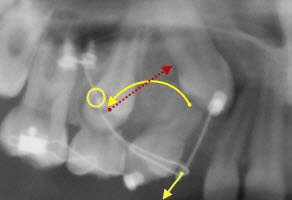

En jaune, la force anti-horaire dont tu parles et la celle qui tracte la canine.

En pointillés rouges : la réaction qui s'oppose à cette dernière.

Le cintrage à concavité supérieure du fil CT8 est du à sa déformation élastique de traction. La force en pointillés rouges s'oppose à cette déformation.